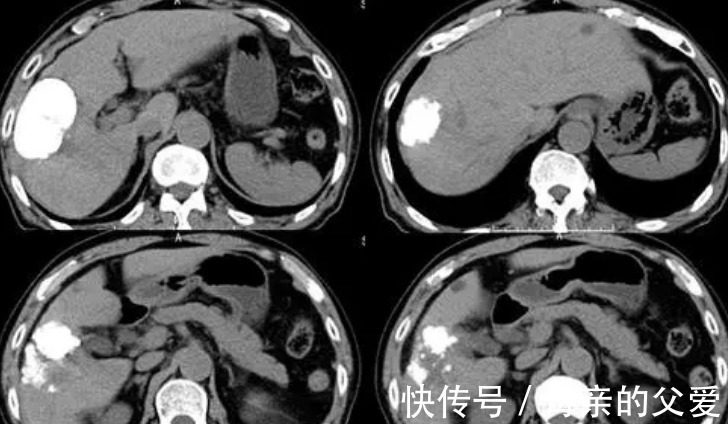

就买了些肠胃药来吃,可是,还没过多久,小丽体重下降得比较厉害,腹部还有隐隐作痛发生,就到医院进行了检查,没成想竟然查出了肝癌。

得知这样的结果,小丽瞬间就崩溃了,没想到自己年纪轻轻就查出了肝癌,随后,经过多次化疗,病情得到了控制,不过,也掏空了家底。